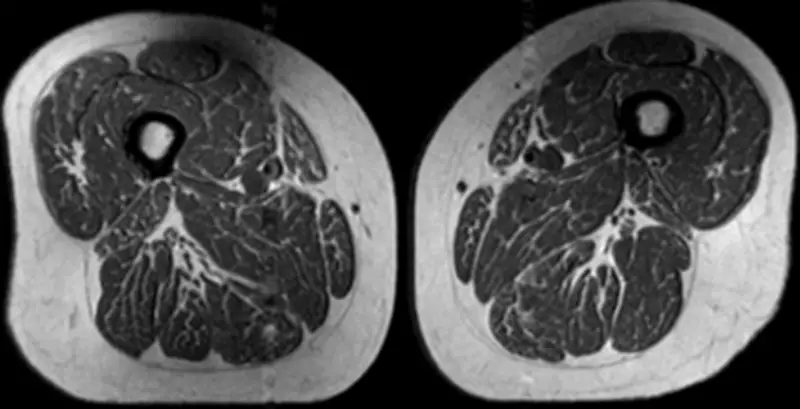

Recent research, highlighted by imaging studies, has demonstrated that individuals with diets consisting predominantly of ultraprocessed foods exhibit significant fat accumulation in their thigh muscles. In one notable case, an MRI scan of a woman whose diet was 87% ultraprocessed revealed extensive fat infiltration within the thigh tissue. This pattern of fat deposition is not merely a cosmetic concern but is associated with a range of serious health issues, including metabolic disorders, cardiovascular diseases, and reduced muscle function.

Experts warn that the convenience and affordability of ultraprocessed foods have made them a staple in many diets, particularly in Western societies. This shift has coincided with rising rates of obesity and related health problems globally. The visual evidence from MRI scans serves as a powerful reminder of the tangible effects of dietary choices on the body's internal structures.